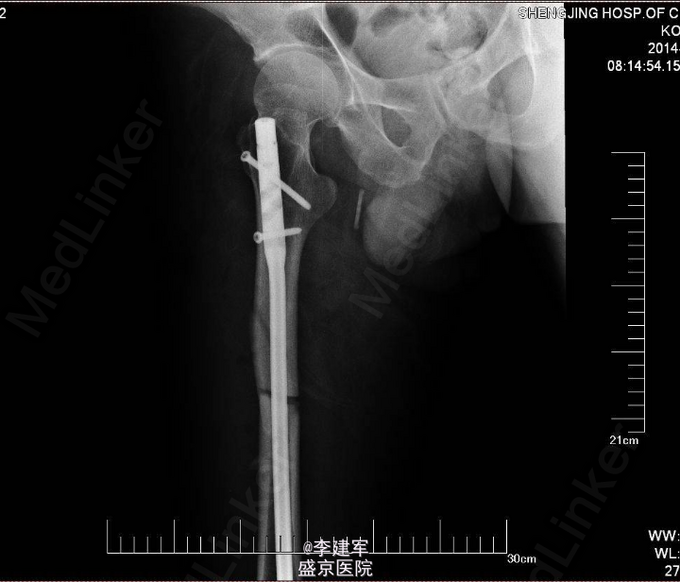

主诉:摔倒后右大腿疼痛肿胀活动受限5小时 现病史:患者家属自述骑自行车自行摔倒,摔倒后右大腿疼痛肿胀,活动受限,伤后患者昏迷约一小时,急诊送入当地医院,DR(当地医院)提示右股骨干骨折,当地医院给予患肢皮牵引固定等对症治疗。今日患者为求进一步手术治疗来我院治疗。门诊以“右股骨干骨折”为诊断收入院。患者病来一般状态可,生命体征平稳,无发热,饮食睡眠可,二便正常。

专科查体:患者平车推入病房,右下肢短缩屈曲中,右大腿疼痛,肿胀明显,可触及反常活动及骨擦感,纵向叩击痛阳性。右大腿外侧可见皮肤瘀斑,右足背动脉搏动正常,足趾活动可,皮肤感觉较健侧无明显异常。

诊断:右股骨干粉碎性骨折 患者右股骨干粉碎性骨折,拟行右股骨干骨折闭合复位内固定术。

长骨的干的骨折,行髓内针闭合复位,有助于患者早期下地行走,且创口小。粉碎性骨折不破坏骨膜,骨的血运未破坏。扩髓相当于髓内植骨,有利于生长。所以本次手术行髓内针闭合复位。